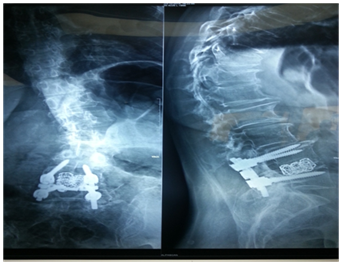

Flat back syndrome

- Loss of Lumbar Lordosis.

- Need an extensive release of the posterior elements with facet joints osteotomy.

- Anterior release MAY also be needed in severely rigid curves.

- Anterior column reconstruction with cages especially at Lumbo- sacral junction is necessary and always required to restore sagittal balance (Figure 3).

Figure 3 Flat back syndrome.